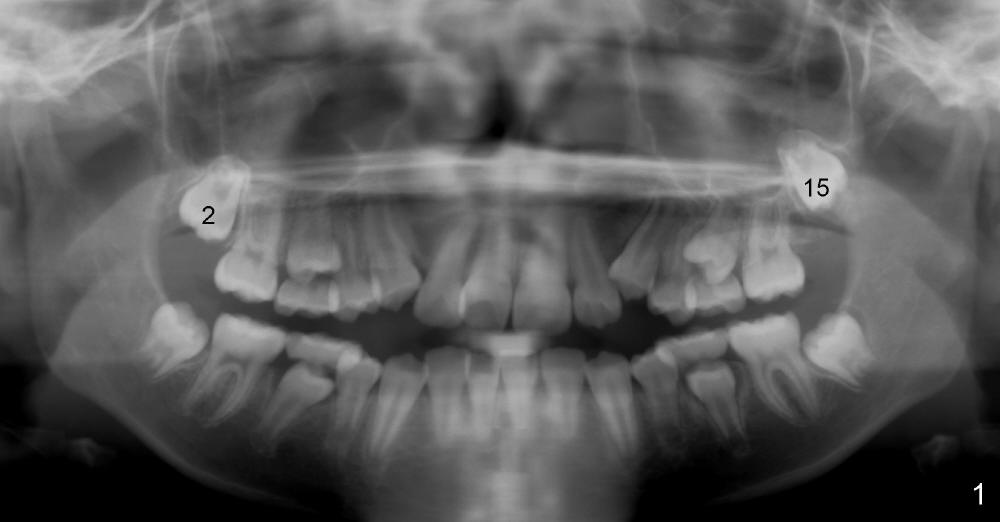

When Willie was 11 years 2 months old, the upper 2nd molars are unerupted (Fig.1: #2,15).

Now at the age of 12 years 10 months, #2 has erupted whereas #15 remains unerupted (Fig.2).